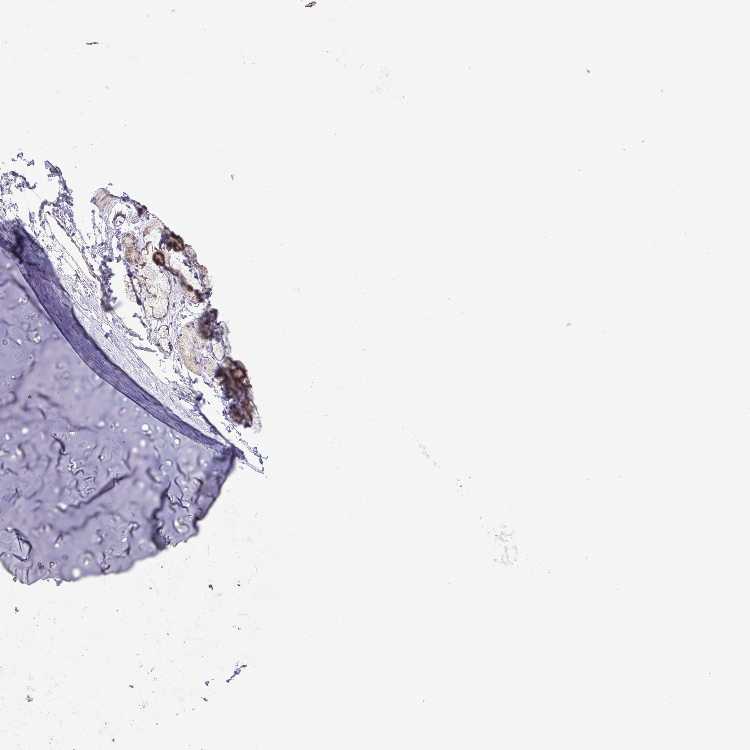

ADIPOSE TISSUE - Antibody stainingi

Antibody staining in the annotated cell types in the current human tissue is reported as not detected, low, medium, or high, based on conventional immunohistochemistry profiling in selected tissues. This score is based on the combination of the staining intensity and fraction of stained cells.

Each image is clickable and will lead to virtual microscopy that enables deeper exploration of all samples and also displays staining intensity scores, fraction scores and subcellular localization as well as patient and tissue information for each sample.

Antibody HPA059251Antibody HPA071866

Adipocytes Not detectedNot detected